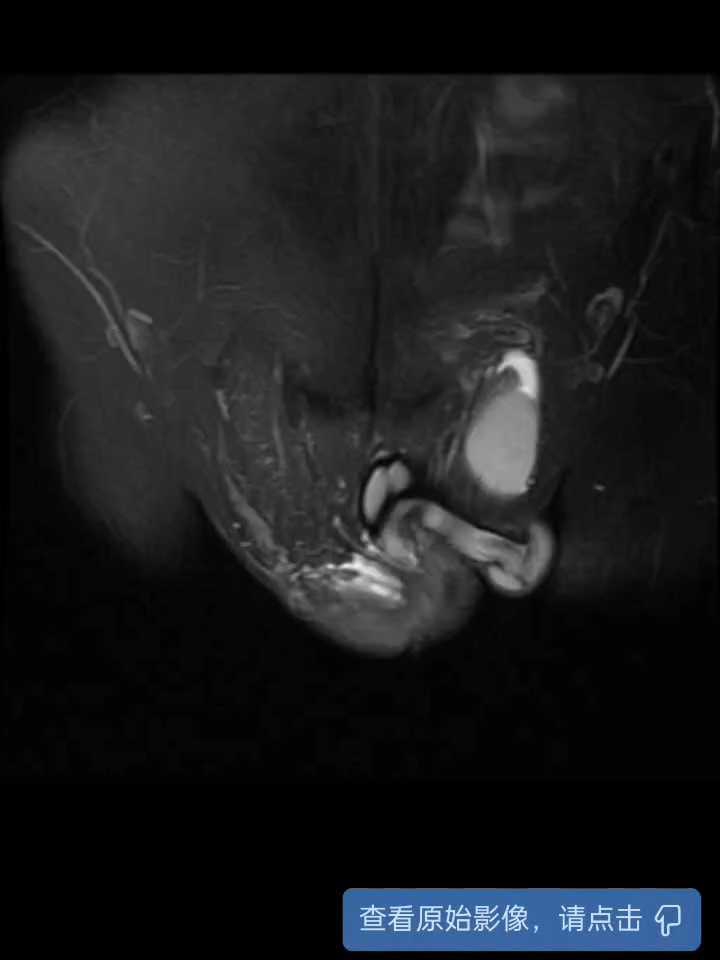

这个手术做的比较狼狈,一开始想给他做剜除,但奈何不好找边界,没有成功,切的过程中还遇到电切环出问题,更换电切环。最后发现还是捅出了篓子,幸好早有所耳闻,腹股沟置管引流出膀胱周围液体,但引出不多,所幸腹腔置管(胆囊周围穿刺点,超声引导下穿刺),引出1000多ml积液。术后安全恢复出院。

对于这种电切后直接出现腹腔积液及膀胱周围积液的,应该就是哪儿切穿了,但总的手术视频没有看出来。最后一个视频没有录制成功,各位大佬将就着看,请多指教。